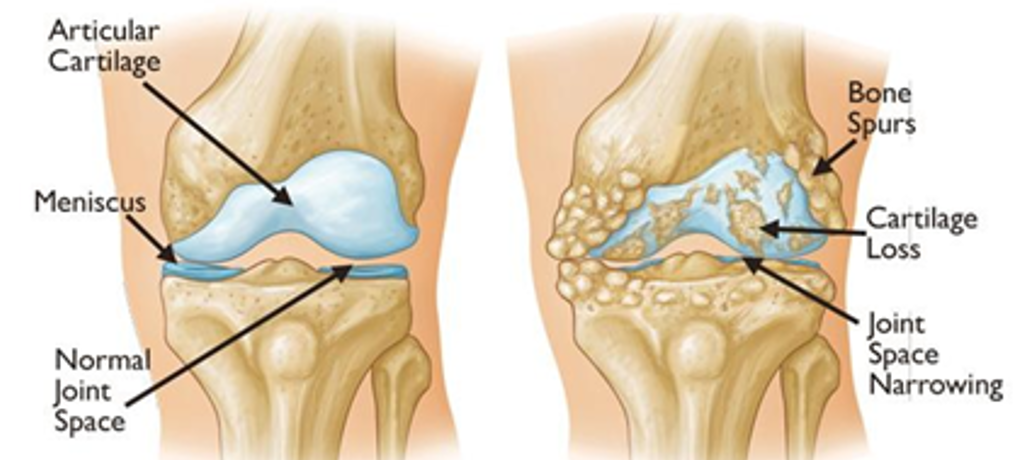

Degenerative Joint Disease/Arthritis

• ________ disease of the knee joint that causes progressive ____ of articular ________.

• Diagnosis can be made with plain (1) of the knee. (advanced imaging is not typically helpful)

• Treatment is observation, NSAIDs, tr_____ and cortico______ for minimally symptomatic patients. Knee (1) is indicated for progressive symptoms with severe degenerative disease.

• Degenerative disease of the knee joint that causes progressive loss of articular cartilage.

• Diagnosis can be made with plain radiographs of the knee. (advanced imaging is not typically helpful)

• Treatment is observation, NSAIDs, tramadol and corticosteroids for minimally symptomatic patients. Knee arthroplasty is indicated for progressive symptoms with severe degenerative disease.

• The most common types of arthritis are osteoarthritis and rheumatoid arthritis, but there are more than 100 different forms.

• I will focus on osteoarthritis

19

Q

Degenerative Joint Disease/Arthritis Imaging

• XR:

• Recommended views

• Weight-______ views of affected joint

• Optional views

• S______ view

• _ _ view in 30 degrees of flexion

• Look for:

• Joint _____ narrowing

• Osteo_____

• Subchondral s______

• Subchondral c_____

• MRI: ______ the urge, especially in advanced disease

• Weight-bearing views of affected joint

• Sunrise view

• PA view in 30 degrees of flexion

• Joint space narrowing

• Osteophytes

• Subchondral sclerosis

• Subchondral cysts

• MRI: Resist the urge, especially in advanced disease